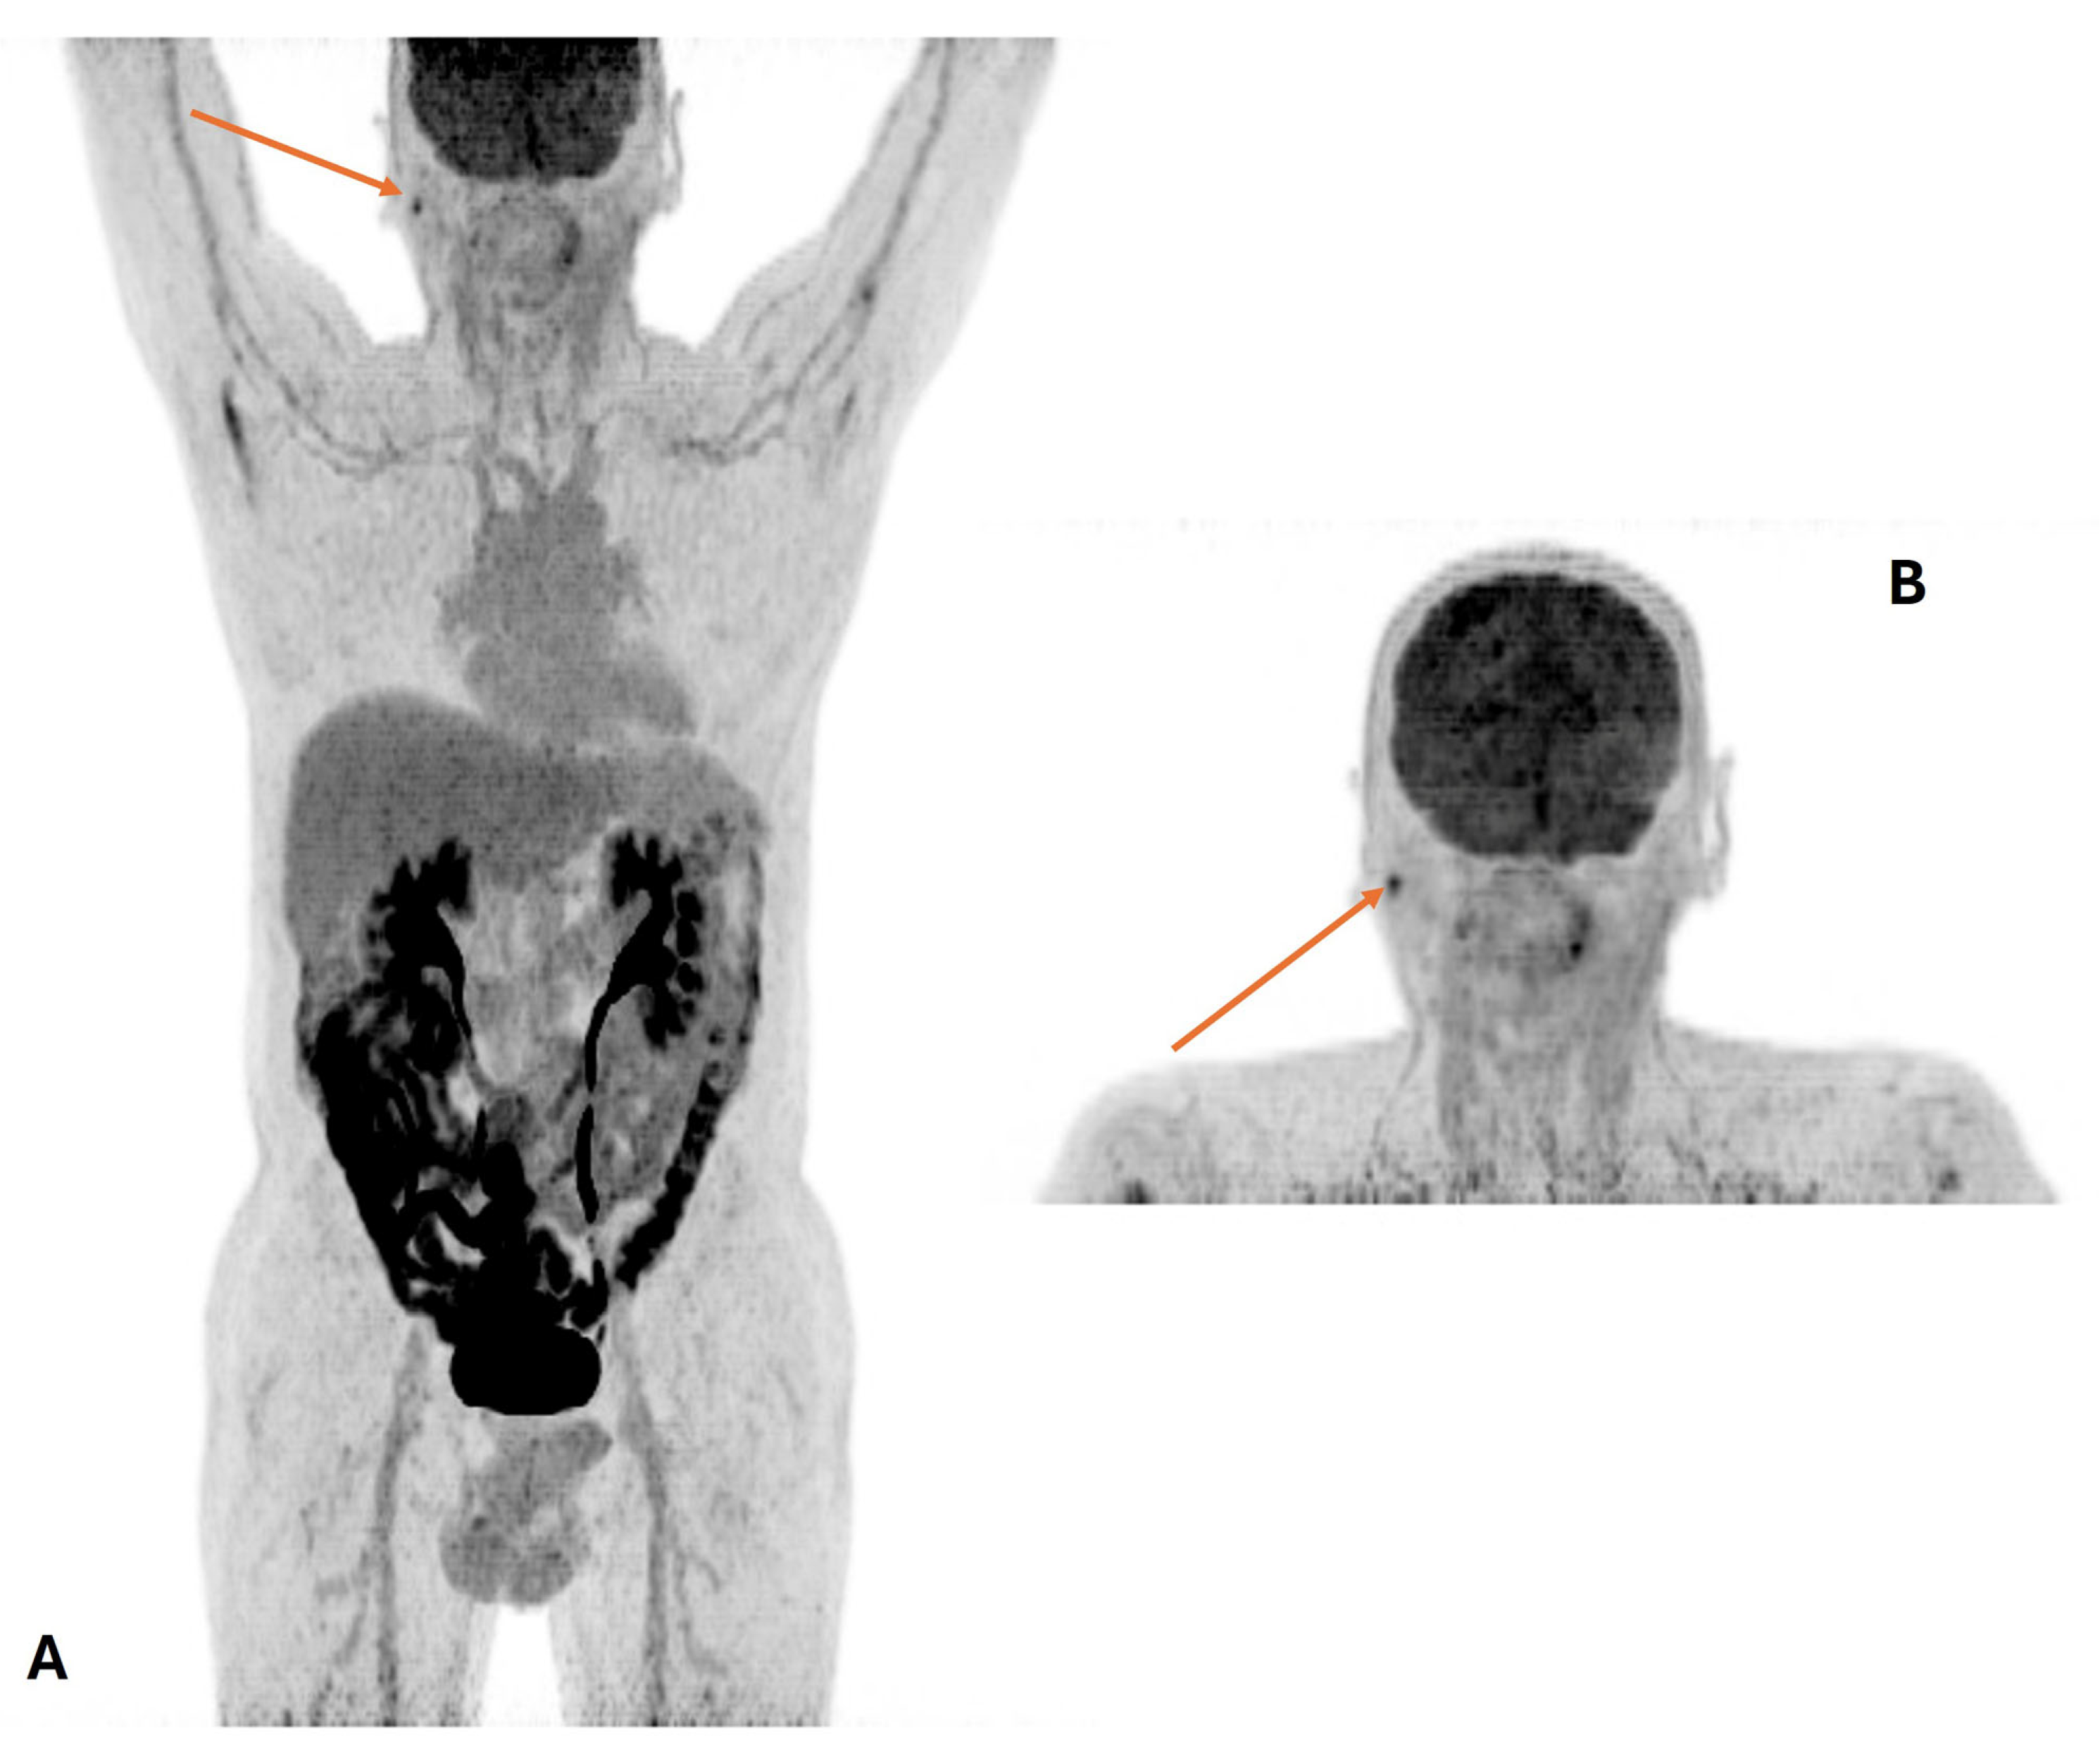

3.3. Distant Metastasis Assessment

- Price, P.M.; Badawi, R.D.; Cherry, S.R.; Jones, T. Ultra staging to unmask the prescribing of adjuvant therapy in cancer patients: The future opportunity to image micrometastases using total-body 18F-FDG PET scanning. J. Nucl. Med. 2014, 55, 696–697. [Google Scholar] [CrossRef]